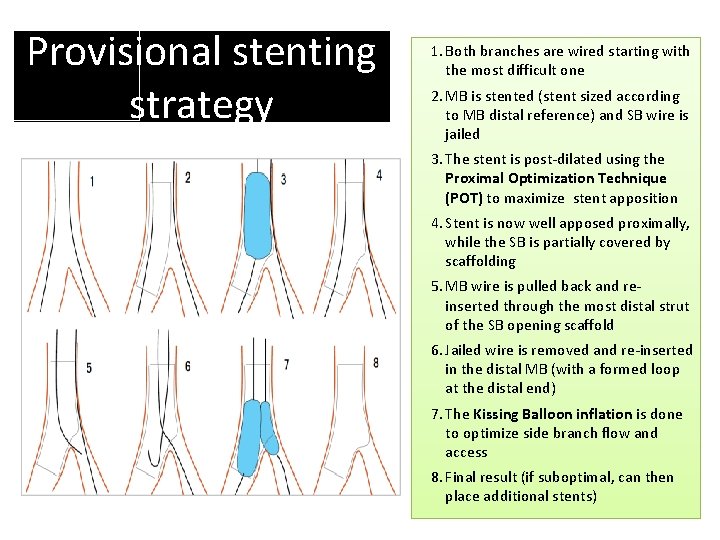

Provisional stenting strategy 1. Both branches are wired starting with the most difficult one 2. MB is stented (stent sized according to MB distal reference) and SB wire is jailed 3. The stent is post-dilated using the Proximal Optimization Technique (POT) to maximize stent apposition 4. Stent is now well apposed proximally, while the SB is partially covered by scaffolding 5. MB wire is pulled back and reinserted through the most distal strut of the SB opening scaffold 6. Jailed wire is removed and re-inserted in the distal MB (with a formed loop at the distal end) 7. The Kissing Balloon inflation is done to optimize side branch flow and access 8. Final result (if suboptimal, can then place additional stents)